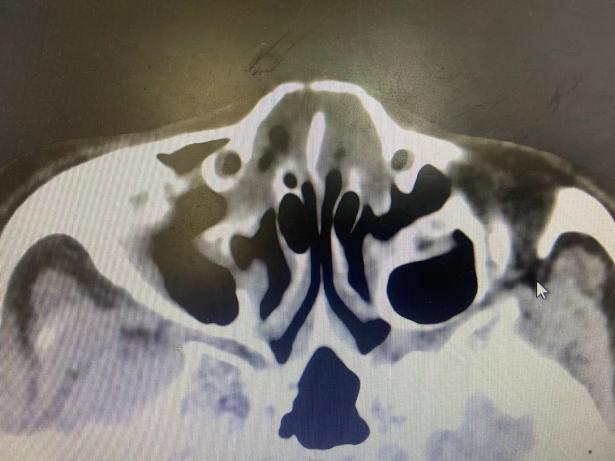

近日,新昌县人民医院耳鼻咽喉科在县内首次开展高频B超引导下的鼻骨骨折整复术。 71岁的薛阿姨(化名),因一场突如其来的车祸,被紧急送入新昌县人民医院。入院后,鼻骨CT检查结果令人揪心:双侧鼻骨骨折,鼻中隔骨折,需进行手术..